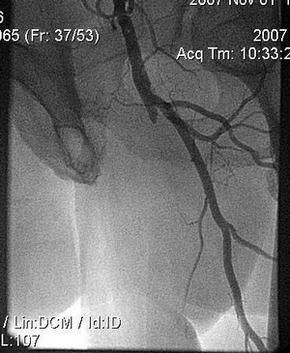

Пациент К, 1940 г.р. (67 лет).

- Распространенный атеросклероз с поражением коронарных артерий, артерий дуги аорты и артерий нижних конечностей.

- Окклюзия правой ВСА, стеноз левой ВСА. Состояния после перенесенных ОНМК.

- Окклюзия обеих ПБА.

- ИБС.

- Стенокардия 2-3 ф.к.

Проведена реканализация левой ПБА гидрофильным проводником, затем баллонная ангиопластика баллоном OptaPro 4х40mm.